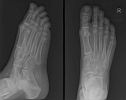

Thorax – Abdomen – Schedel – CWZ – DWZ – LWZ – Bekken – Full Spine – Schouder – Bovenarm – Elleboog – Onderarm – Pols – Hand – Heup – Bovenbeen – Knie – Onderbeen – Enkel – Voet – Full Leg – Transit – Colonografie – E.R.C.P. – I.V.P. – Cystografie – Hysterografie

Enkel